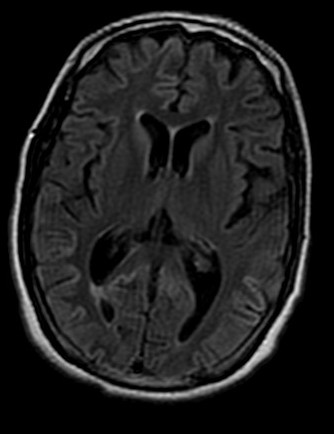

View Creutzfeldt-Jakob Disease Vs Normal Brain PNG. Over time, the disease causes growing problems with memory, personality changes, and dementia. It affects about one person in every one million people per year worldwide;